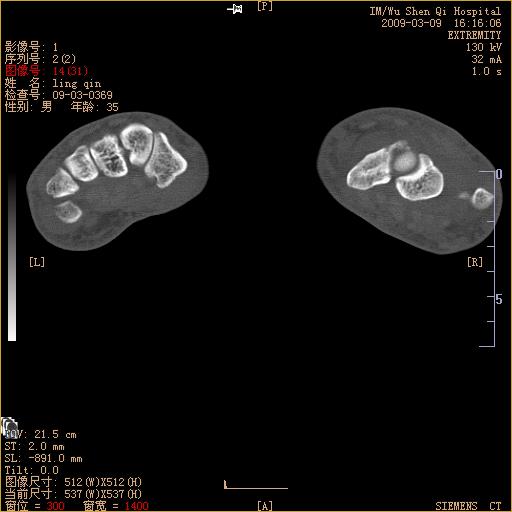

标题: CT18570:右手外伤10余天 [打印本页]

标题: CT18570:右手外伤10余天

腕部有骨折、脱位,骨科面对ct片如何采取措施?三维一下。

左侧舟骨及桡骨茎突骨折,第一掌骨基底部好像也有骨折,建议上传平片